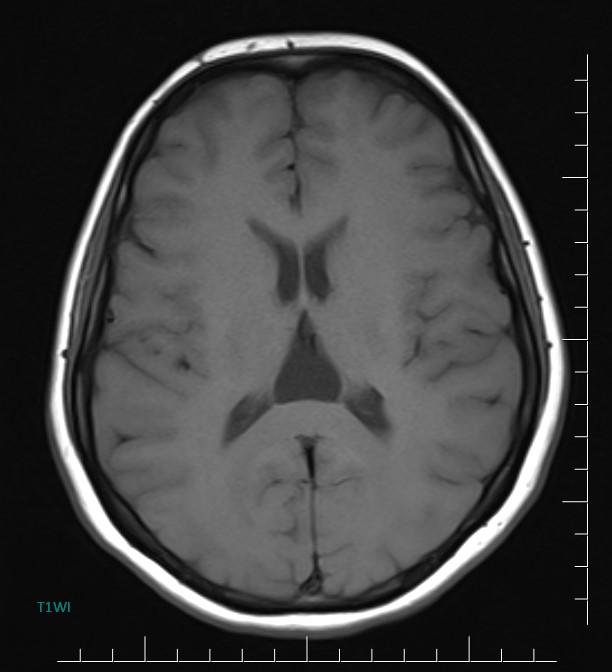

MR images incidentally revealed a triangular-shaped CSF space between the lateral ventricles (arrows).

Axial MR/CT image shows a triangular-shaped CSF space situated behind the foramen of Monro, between the lateral ventricles. Coronal image demonstrates the elevated and splayed fornices.